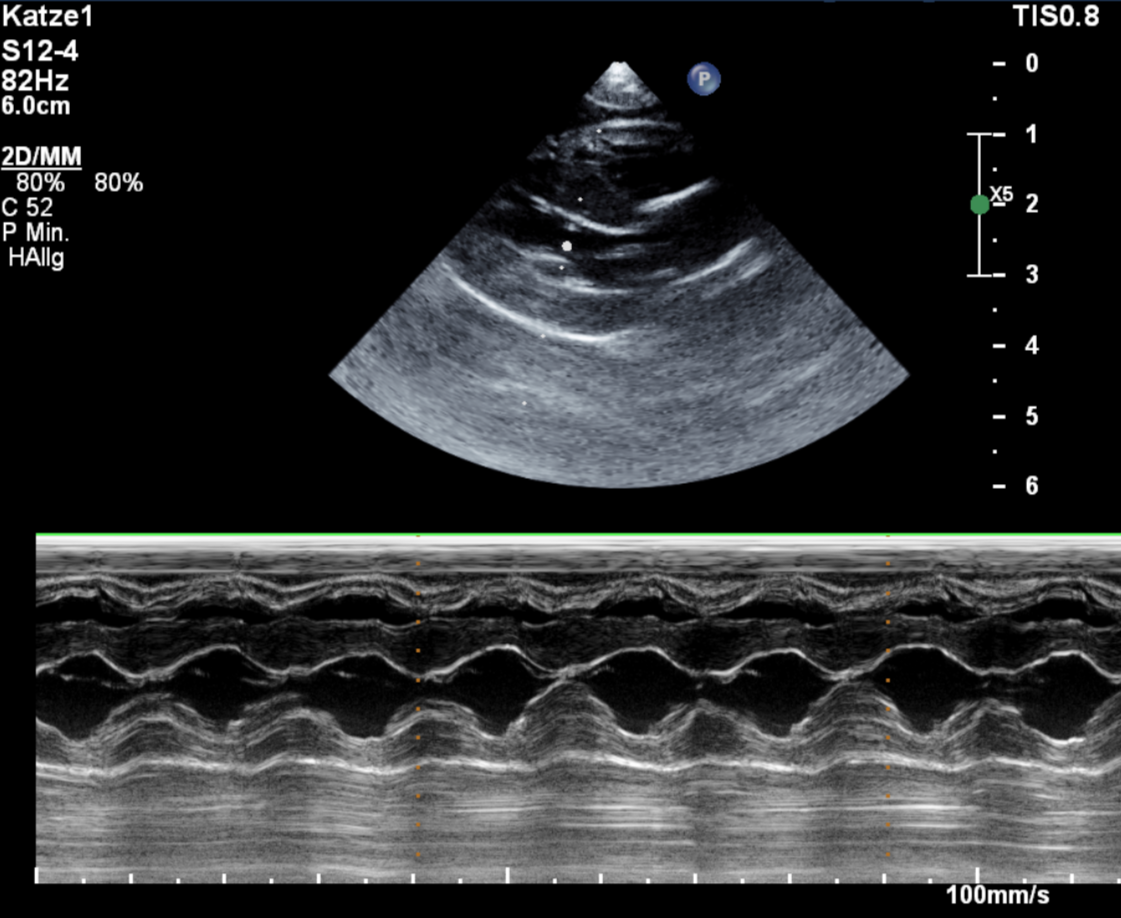

Als Maincoon-Kater Emil in die Praxis kam, dachten alle zuerst seine hochgradig erschwerte Atmung kam von einem Herzleiden mit Pleuraerguss (Flüssigkeit zwischen den Lungenlappen), welche unbehandelt zum Erstickungstod führt. Aber Emil „überraschte“ uns mit einem Pyothorax, d.h. Eiter im Brustkorb. Die Ursache hierfür blieb sein Geheimnis, sowohl kleine Verletzungen als auch Grannen können soetwas auslösen. Nach dem Legen einer Thoraxdrainage und mehrfach täglichem Spülen ging es Emil zum Glück stetig besser, sodass er nach ca. 10 Tagen wieder entlassen werden konnte. Im Nachgang muss er noch mehrere Wochen Antibiotika nehmen, damit es nicht zu einem Rezidiv kommt. Sein Herz ist zum Glück völlig ohne Anzeichen einer HCM (Hypertrophen Kardiomyopathie) und wird in noch lange bei seinen Abenteuern tatkräftig unterstützen.